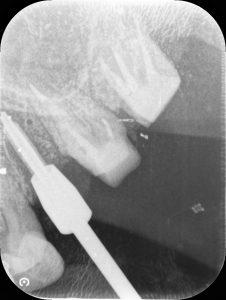

2件目の様子です。

こちらの患者様は、過去に何度かインプラント手術を経験されている方でしたので、落ち着いた様子でオペを受けて頂けたようでした。